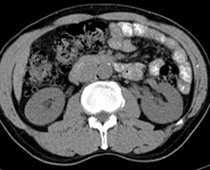

患者,男,57,常年不吃午饭,近一个月来腹部隐痛,无明显黄疸,明天进行增强扫描,图象另上传,麻烦各位帮忙一起看看讨论讨论

肝外胆管扩张,胰头增大,肠系膜上静脉似有包埋征象。

考虑:胰头占位性病变,建议增强进一步检查。

肝外胆管扩张,胰头增大,占位性病变可能性大.

肝外胆管稍扩张,胰腺钩突略增大,但外形尚可,境界清楚。(常年不吃午饭)提示胰腺炎可能大,肿瘤第二步考虑。

支持考胰头占位性病变,感觉十二指肠壁不规则增厚,不排除十二指肠降部占位可炎症

胰头增大,考虑胰头占位性病变。

胰头增大,胆总管增宽,考虑胰头癌可能性大,明天看增强片有助诊断.